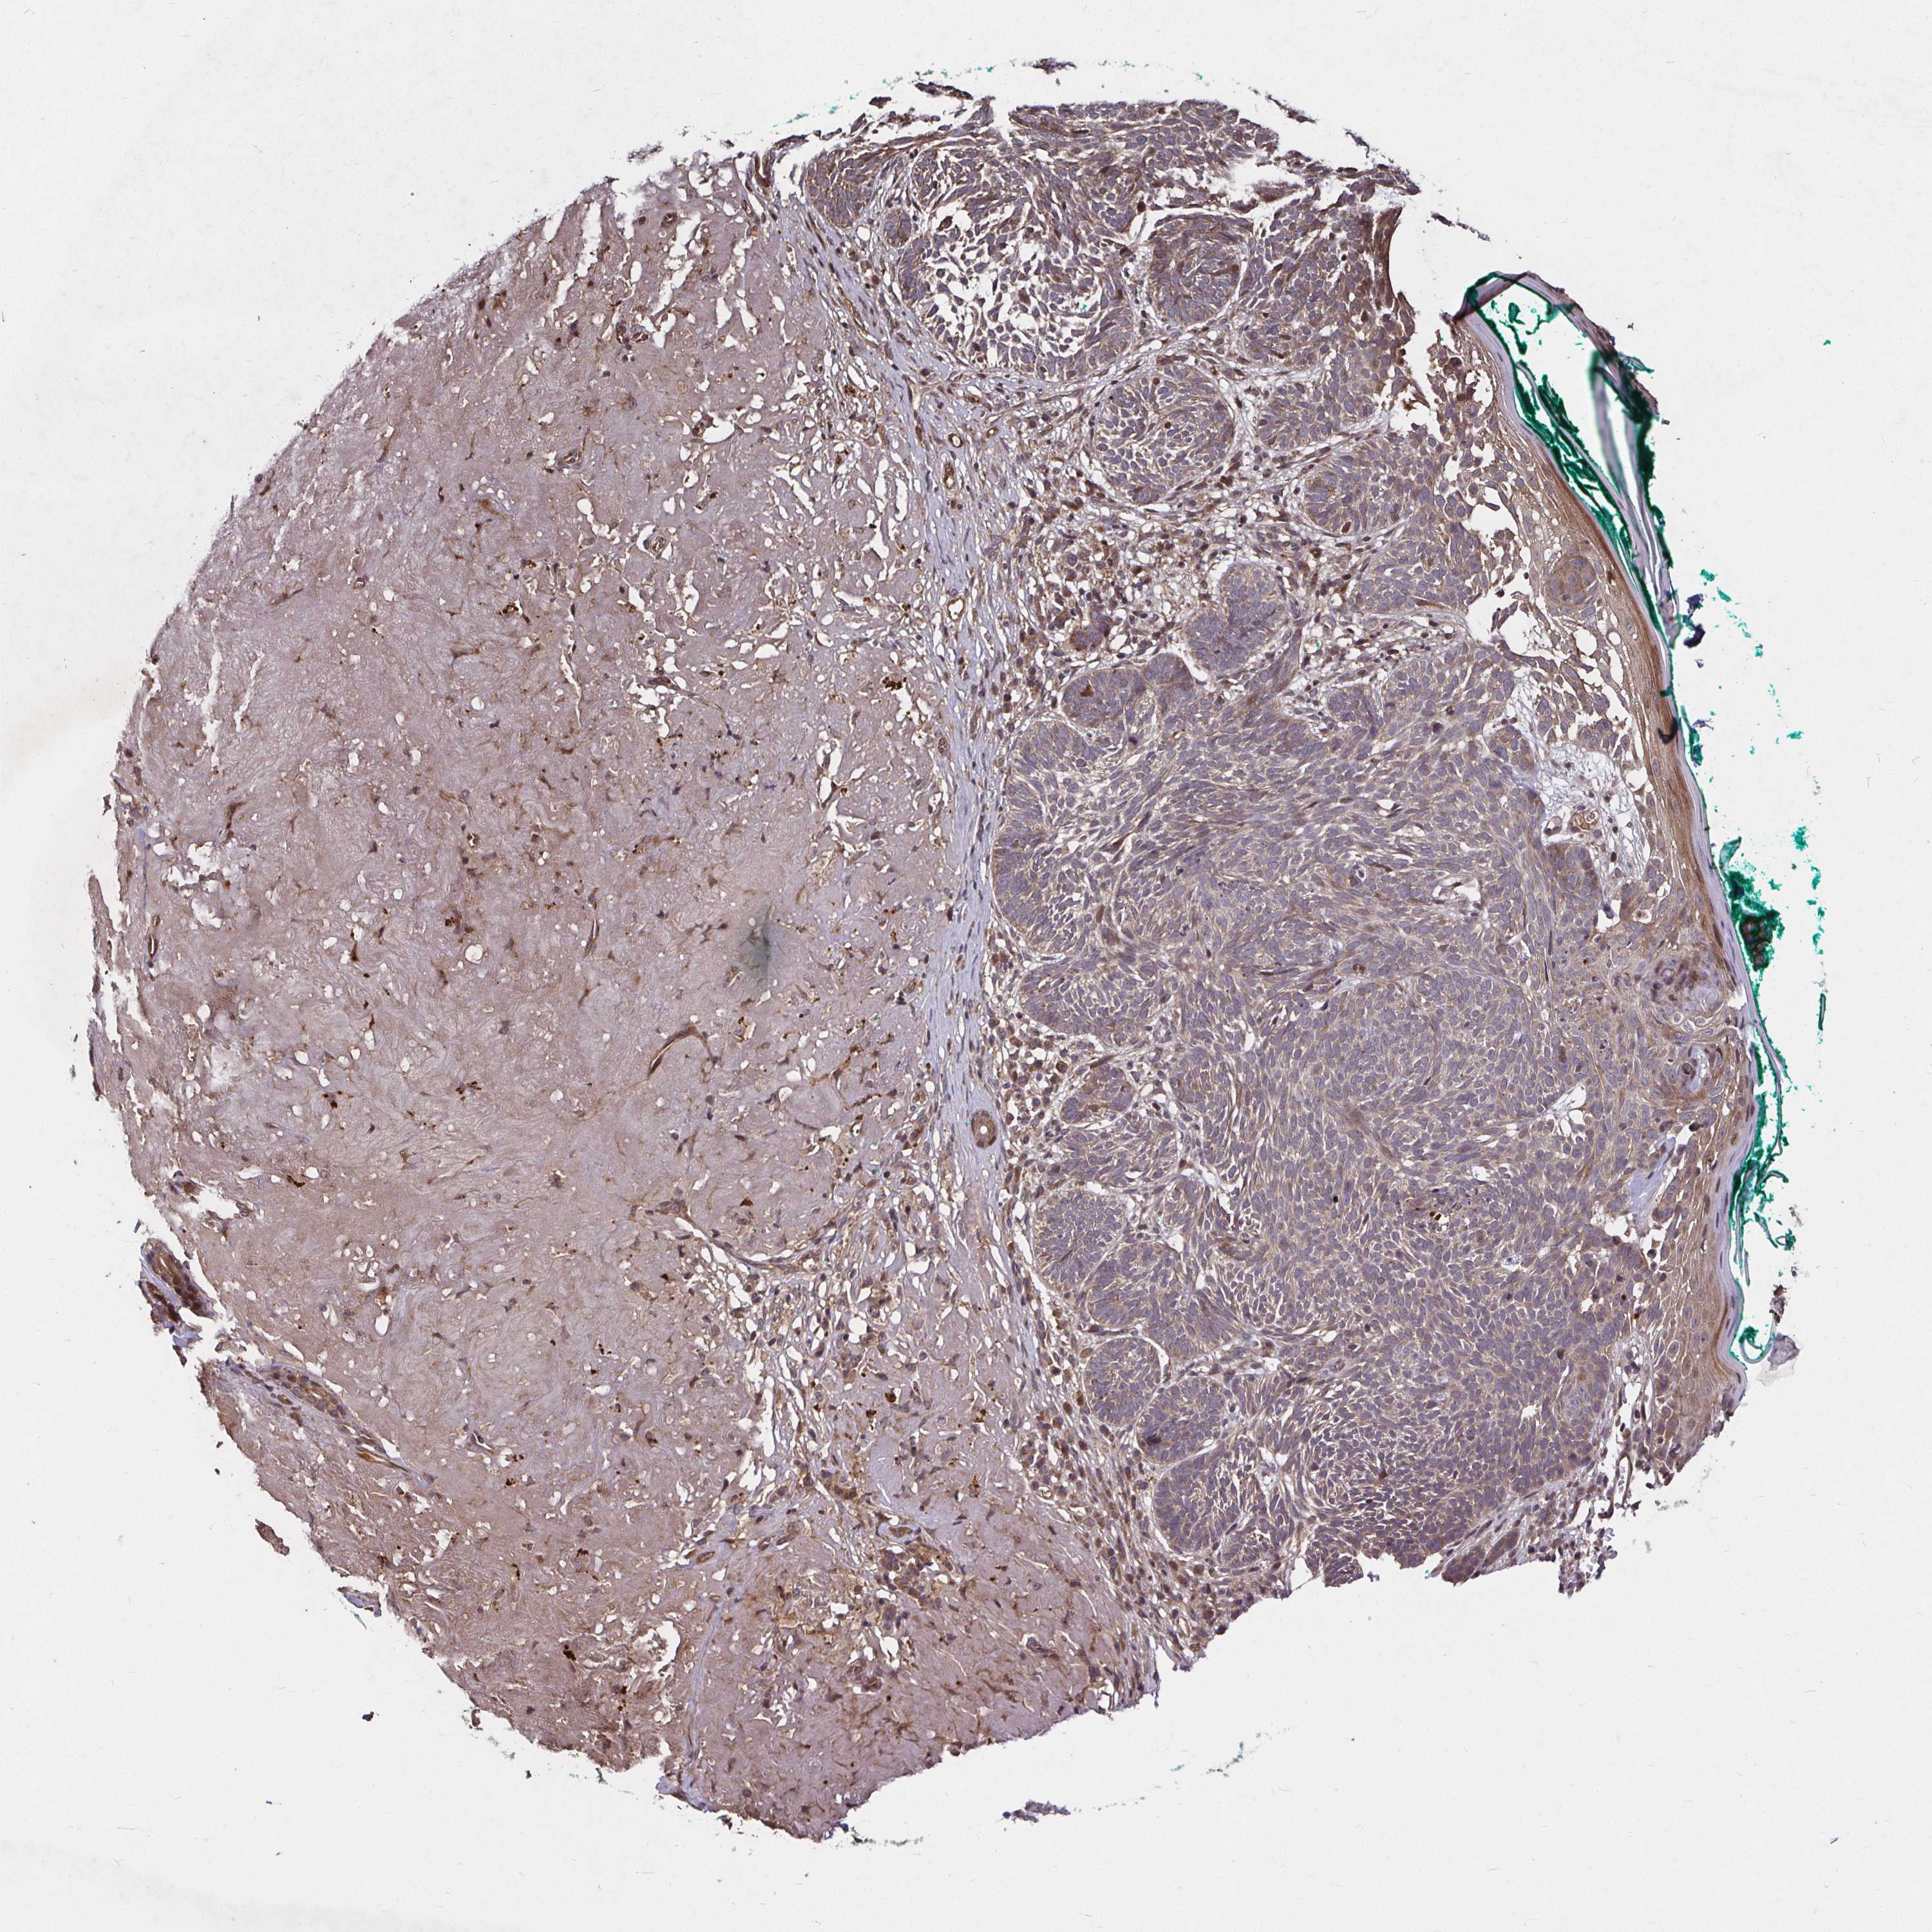

CANCER SKIN CANCER Show tissue menu

SKIN CANCER - Protein expressioni

A mouse-over function shows sample information and annotation data. Click on an image to view it in a full screen mode. Samples can be filtered based on level of antibody staining by selecting one or several of the following categories: high, medium, low and not detected. The assay and annotation is described here.

Each image is clickable and will lead to virtual microscopy that enables deeper exploration of all samples and also displays staining intensity scores, fraction scores and subcellular localization as well as patient and tissue information for each sample.

Antibody HPA045821

Antibody HPA054352

Antibody CAB012229

Basal cell carcinoma

Squamous cell carcinoma, NOS